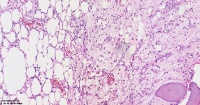

请教老师们这些巨细胞有什么临床意义?

性别

女

年龄

61岁

临床诊断

股骨头骨折

一般病史

标本名称

股骨头组织

大体所见

股骨头骨折处组织

多核吞噬细胞,有纤维素性坏死

是一种反应性改变。